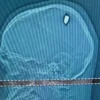

Dikira Kena Lemparan Batu, Ternyata Peluru 9 Milimeter Bersarang di Kepala Selama 4 Hari, Pria Ini Hidup

SEORANG pria di Brazil menganggap dirinya beruntung lantaran masih hidup setelah mengira tembakan di kepalanya sebagai sebuah pukulan batu. Peristiwa...